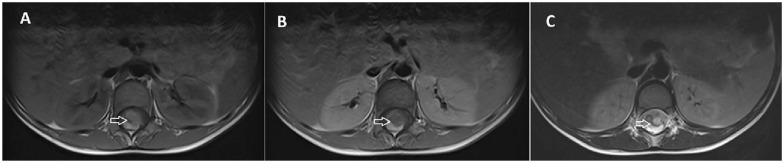

脊柱畸胎瘤虽然在脊柱肿瘤中很少见,但在硬膜内-髓内病变的鉴别诊断中应予以考虑,特别是在出现泌尿和粪便症状的儿童中。全面的影像学评估,包括CT和MRI的特征性发现,如囊性和实性成分,脂肪组织的存在,以及相关的脊髓异常,如鼻咽形成,可以帮助早期诊断。手术切除仍然是治疗的主要方法,及时干预对于预防进展和减轻患者的症状至关重要。在这里,我们讨论一个病例硬膜内-髓内畸胎瘤在一个6岁的儿童谁是及时诊断通过CT和MRI和治疗全手术切除。

Spinal teratomas, though rare among spinal tumors, should be considered in the differential diagnosis of intradural-intramedullary lesions, especially in children presenting with urinary and fecal symptoms. Comprehensive imaging evaluation, including CT and MRI with characteristic findings such as cystic and solid components, the presence of fatty tissue, and associated spinal cord abnormalities like syrinx formation, can aid in early diagnosis. Surgical resection remains the mainstay of treatment, and prompt intervention is crucial to prevent progression and alleviate symptoms in affected patients. Here, we discuss a case of an intradural-intramedullary teratoma in a 6-year-old child who was timely diagnosed using CT and MRI and treated with total surgical resection.